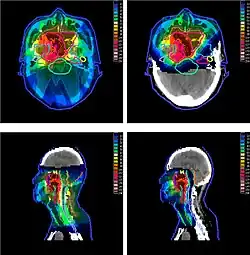

Irradiation of nasopharyngeal carcinoma by photon (X-ray) therapy (left) and proton therapy (right)

The figure at the right of the page shows how beams of X-rays (IMRT; left frame) and beams of protons (right frame), of different energies, penetrate human tissue. A tumor with a sizable thickness is covered by the IMRT spread out Bragg peak (SOBP) shown as the red lined distribution in the figure. The SOBP is an overlap of several pristine Bragg peaks (blue lines) at staggered depths.